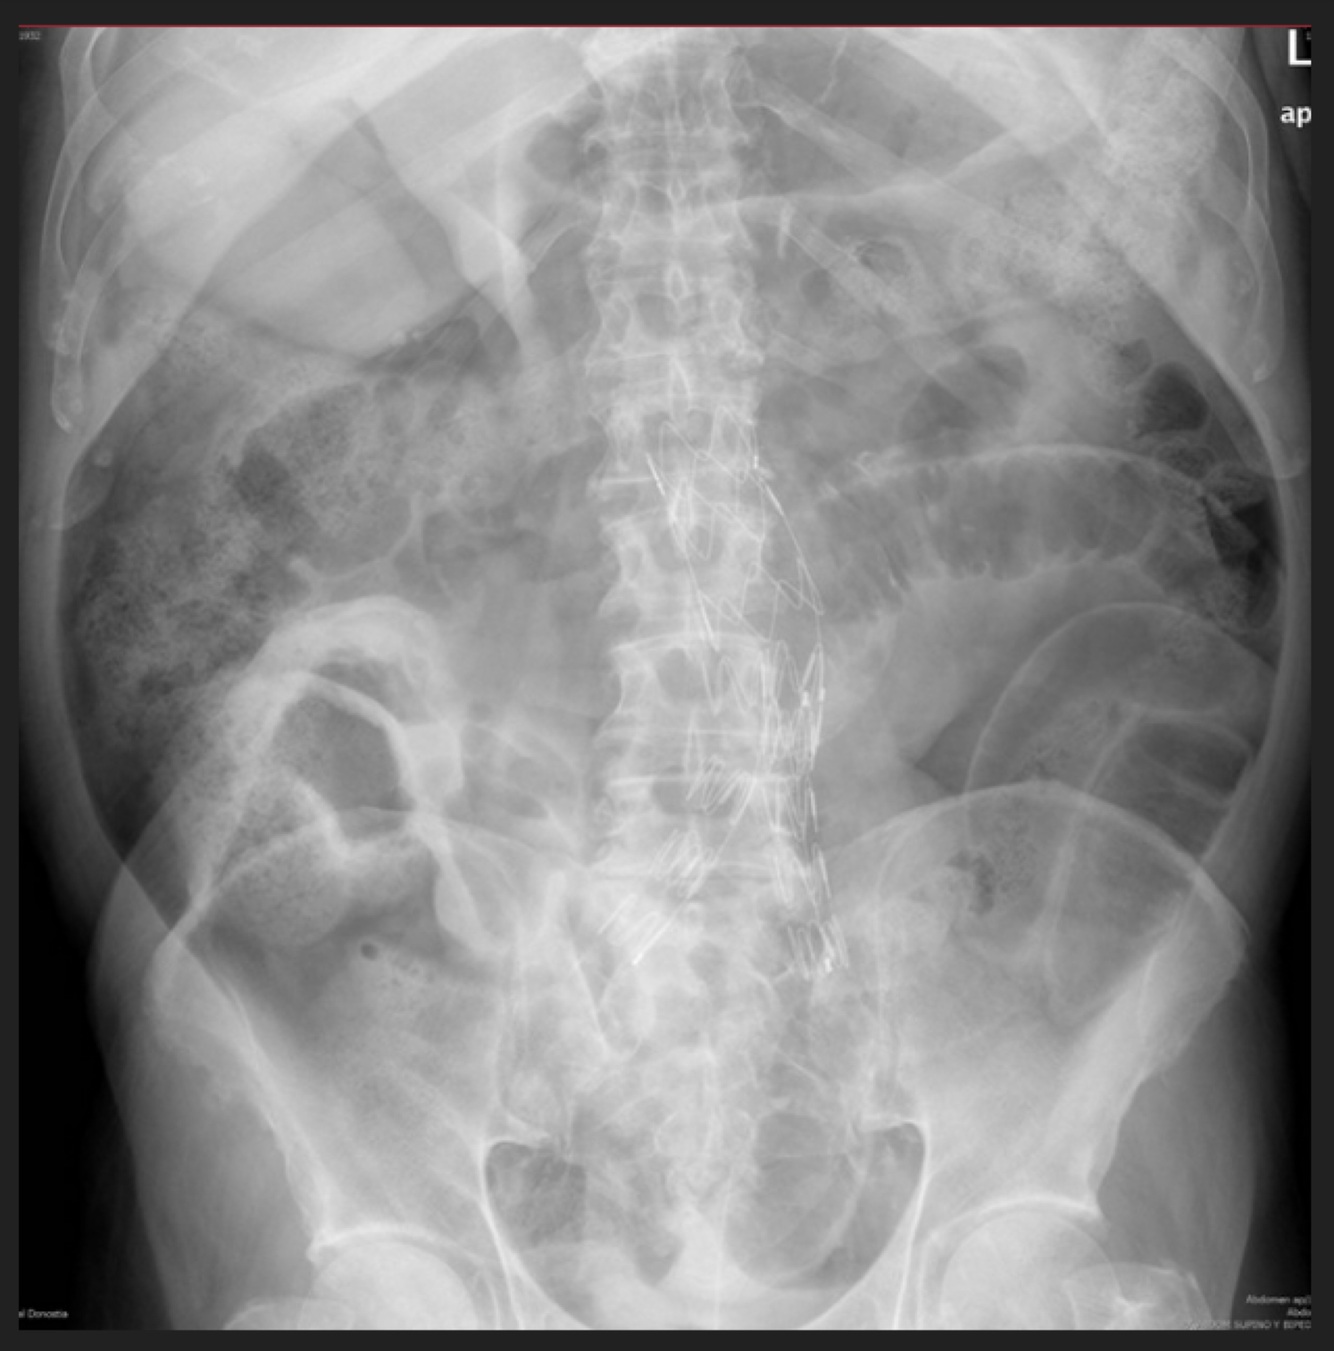

Femenino de 68 años. Dolor abdominal, distensión abdominal, imposibilidad para evacuación y canalización de gases 18 hrs

A

Oclusión intestinal